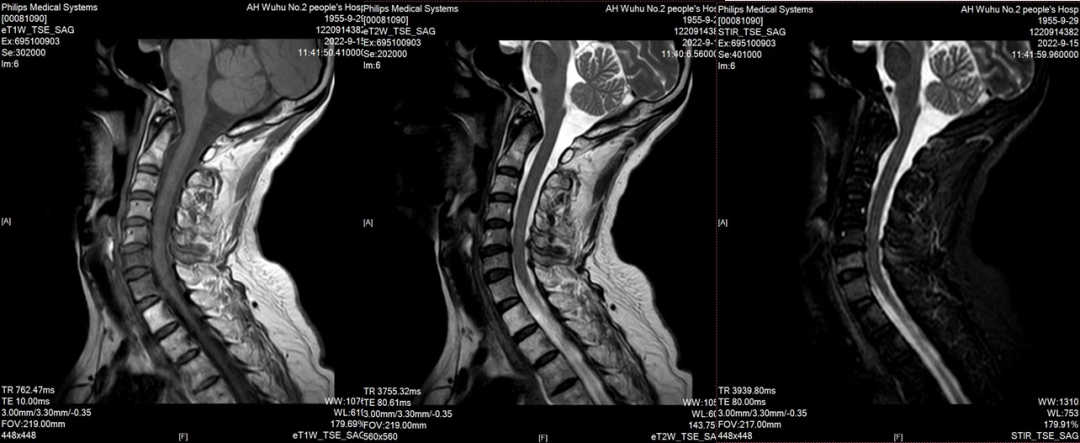

2020-08-05至2020-12-30,予患者EC(多柔比星脂质体+环磷酰胺)-TH(多西他赛+曲妥珠单抗)化疗8周期,后于2021-02-02起予以术后辅助放疗,95%PTV:50Gy/2Gy/25F,期间继续予以曲妥珠单抗靶向维持治疗,持续1年后予吡咯替尼强化治疗,因患者出现严重腹泻,不良反应难以耐受而中断用药;2022年9月患者出现颈部疼痛,完善颈椎MRI平扫提示颈5、6、7及胸1椎体转移,为进一步治疗入院。

2022-9-15颈椎MRI平扫